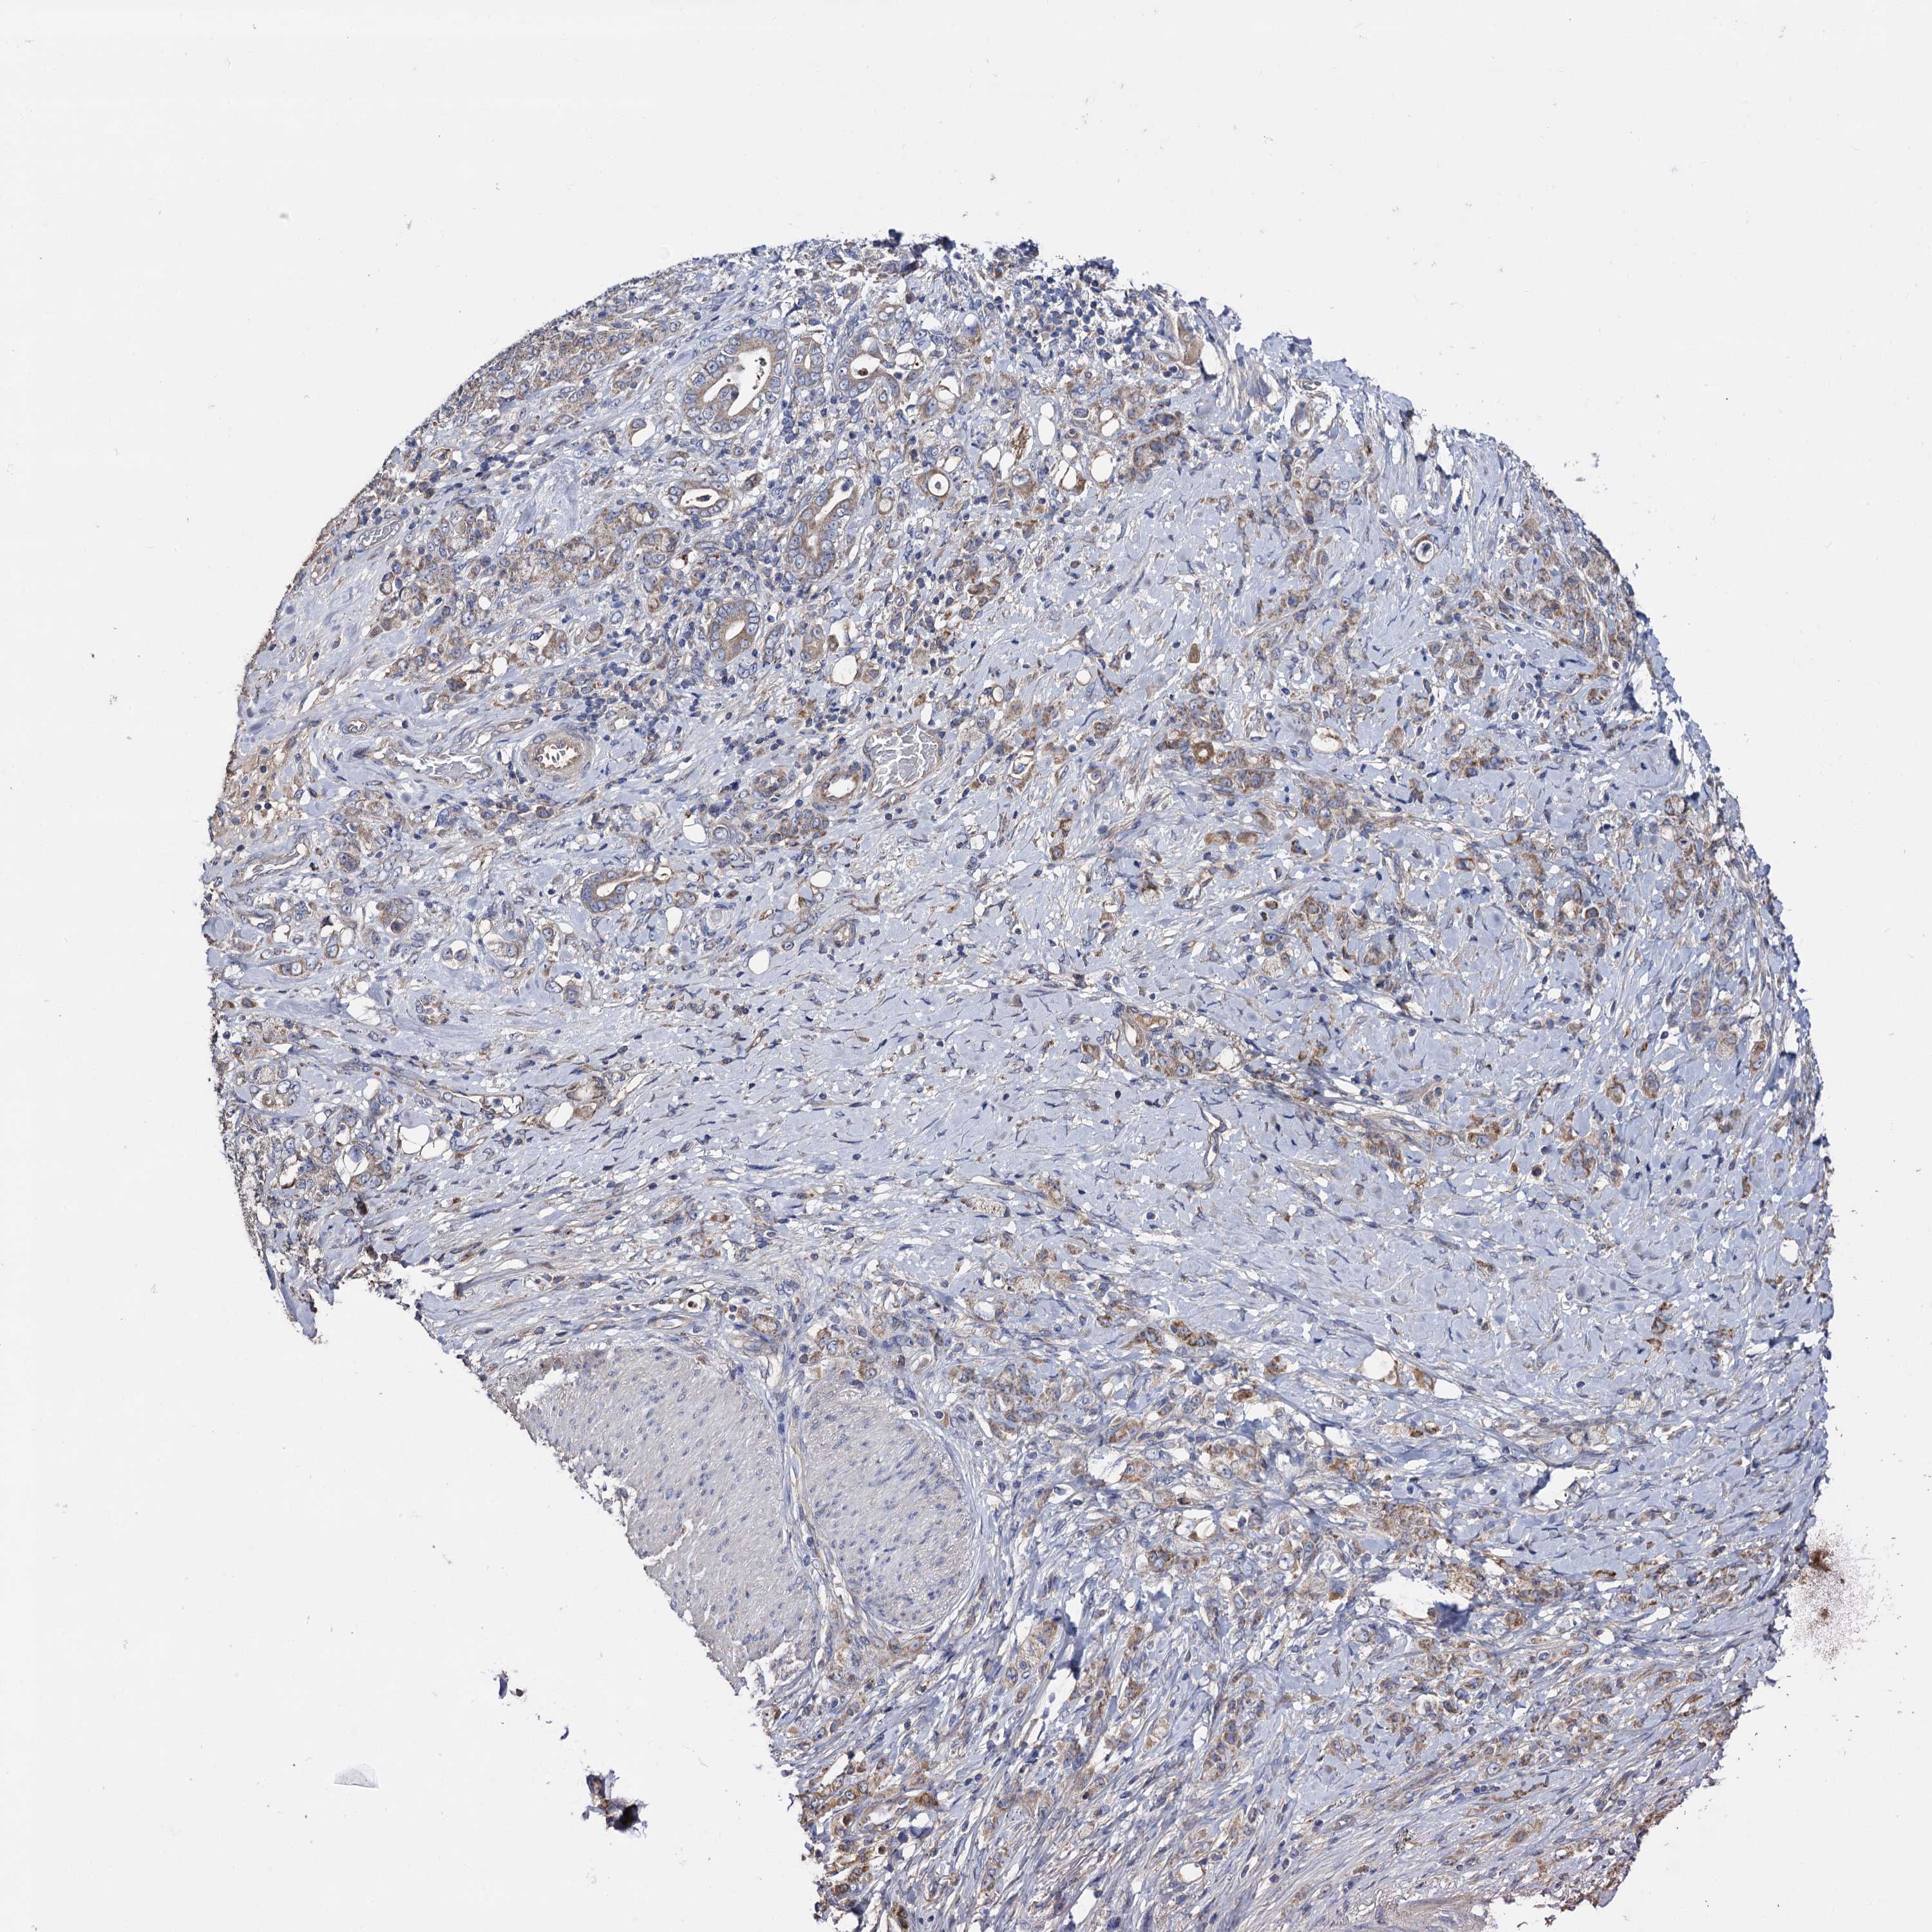

STOMACH CANCER - Protein expressioni

A mouse-over function shows sample information and annotation data. Click on an image to view it in a full screen mode. Samples can be filtered based on level of antibody staining by selecting one or several of the following categories: high, medium, low and not detected. The assay and annotation is described here.

Note that samples used for immunohistochemistry by the Human Protein Atlas do not correspond to samples in the TCGA dataset.

Antibody stainingi

Antibody staining in the annotated cell types in the current human tissue is reported as not detected, low, medium, or high, based on conventional immunohistochemistry profiling in selected tissues. This score is based on the combination of the staining intensity and fraction of stained cells.

Each image is clickable and will lead to virtual microscopy that enables deeper exploration of all samples and also displays staining intensity scores, fraction scores and subcellular localization as well as patient and tissue information for each sample.

Antibody HPA040845

Staining

High

Medium

Low

Not detected

Intensity

Strong

Moderate

Weak

Negative

Quantity

>75%

75%-25%

<25%

None

Location

Nuclear

Cytoplasmic/membranous

Cytoplasmic/membranous,nuclear

Adenocarcinoma, NOS

Adenocarcinoma, High grade